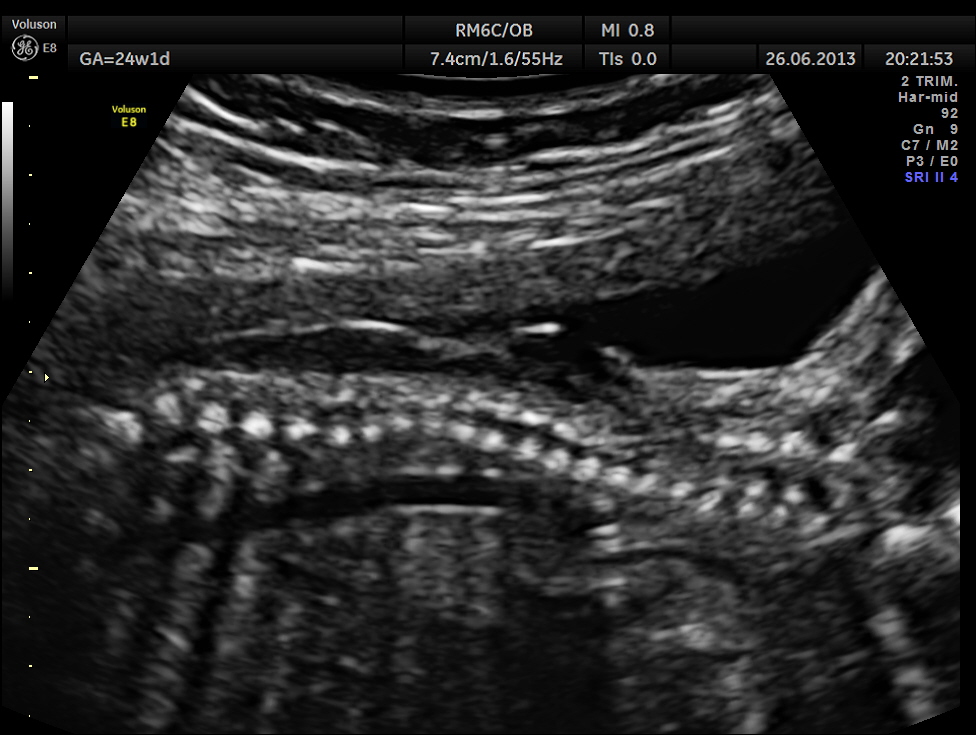

The spine was scanned next and the following images were seen

the following images are reconstructed images.